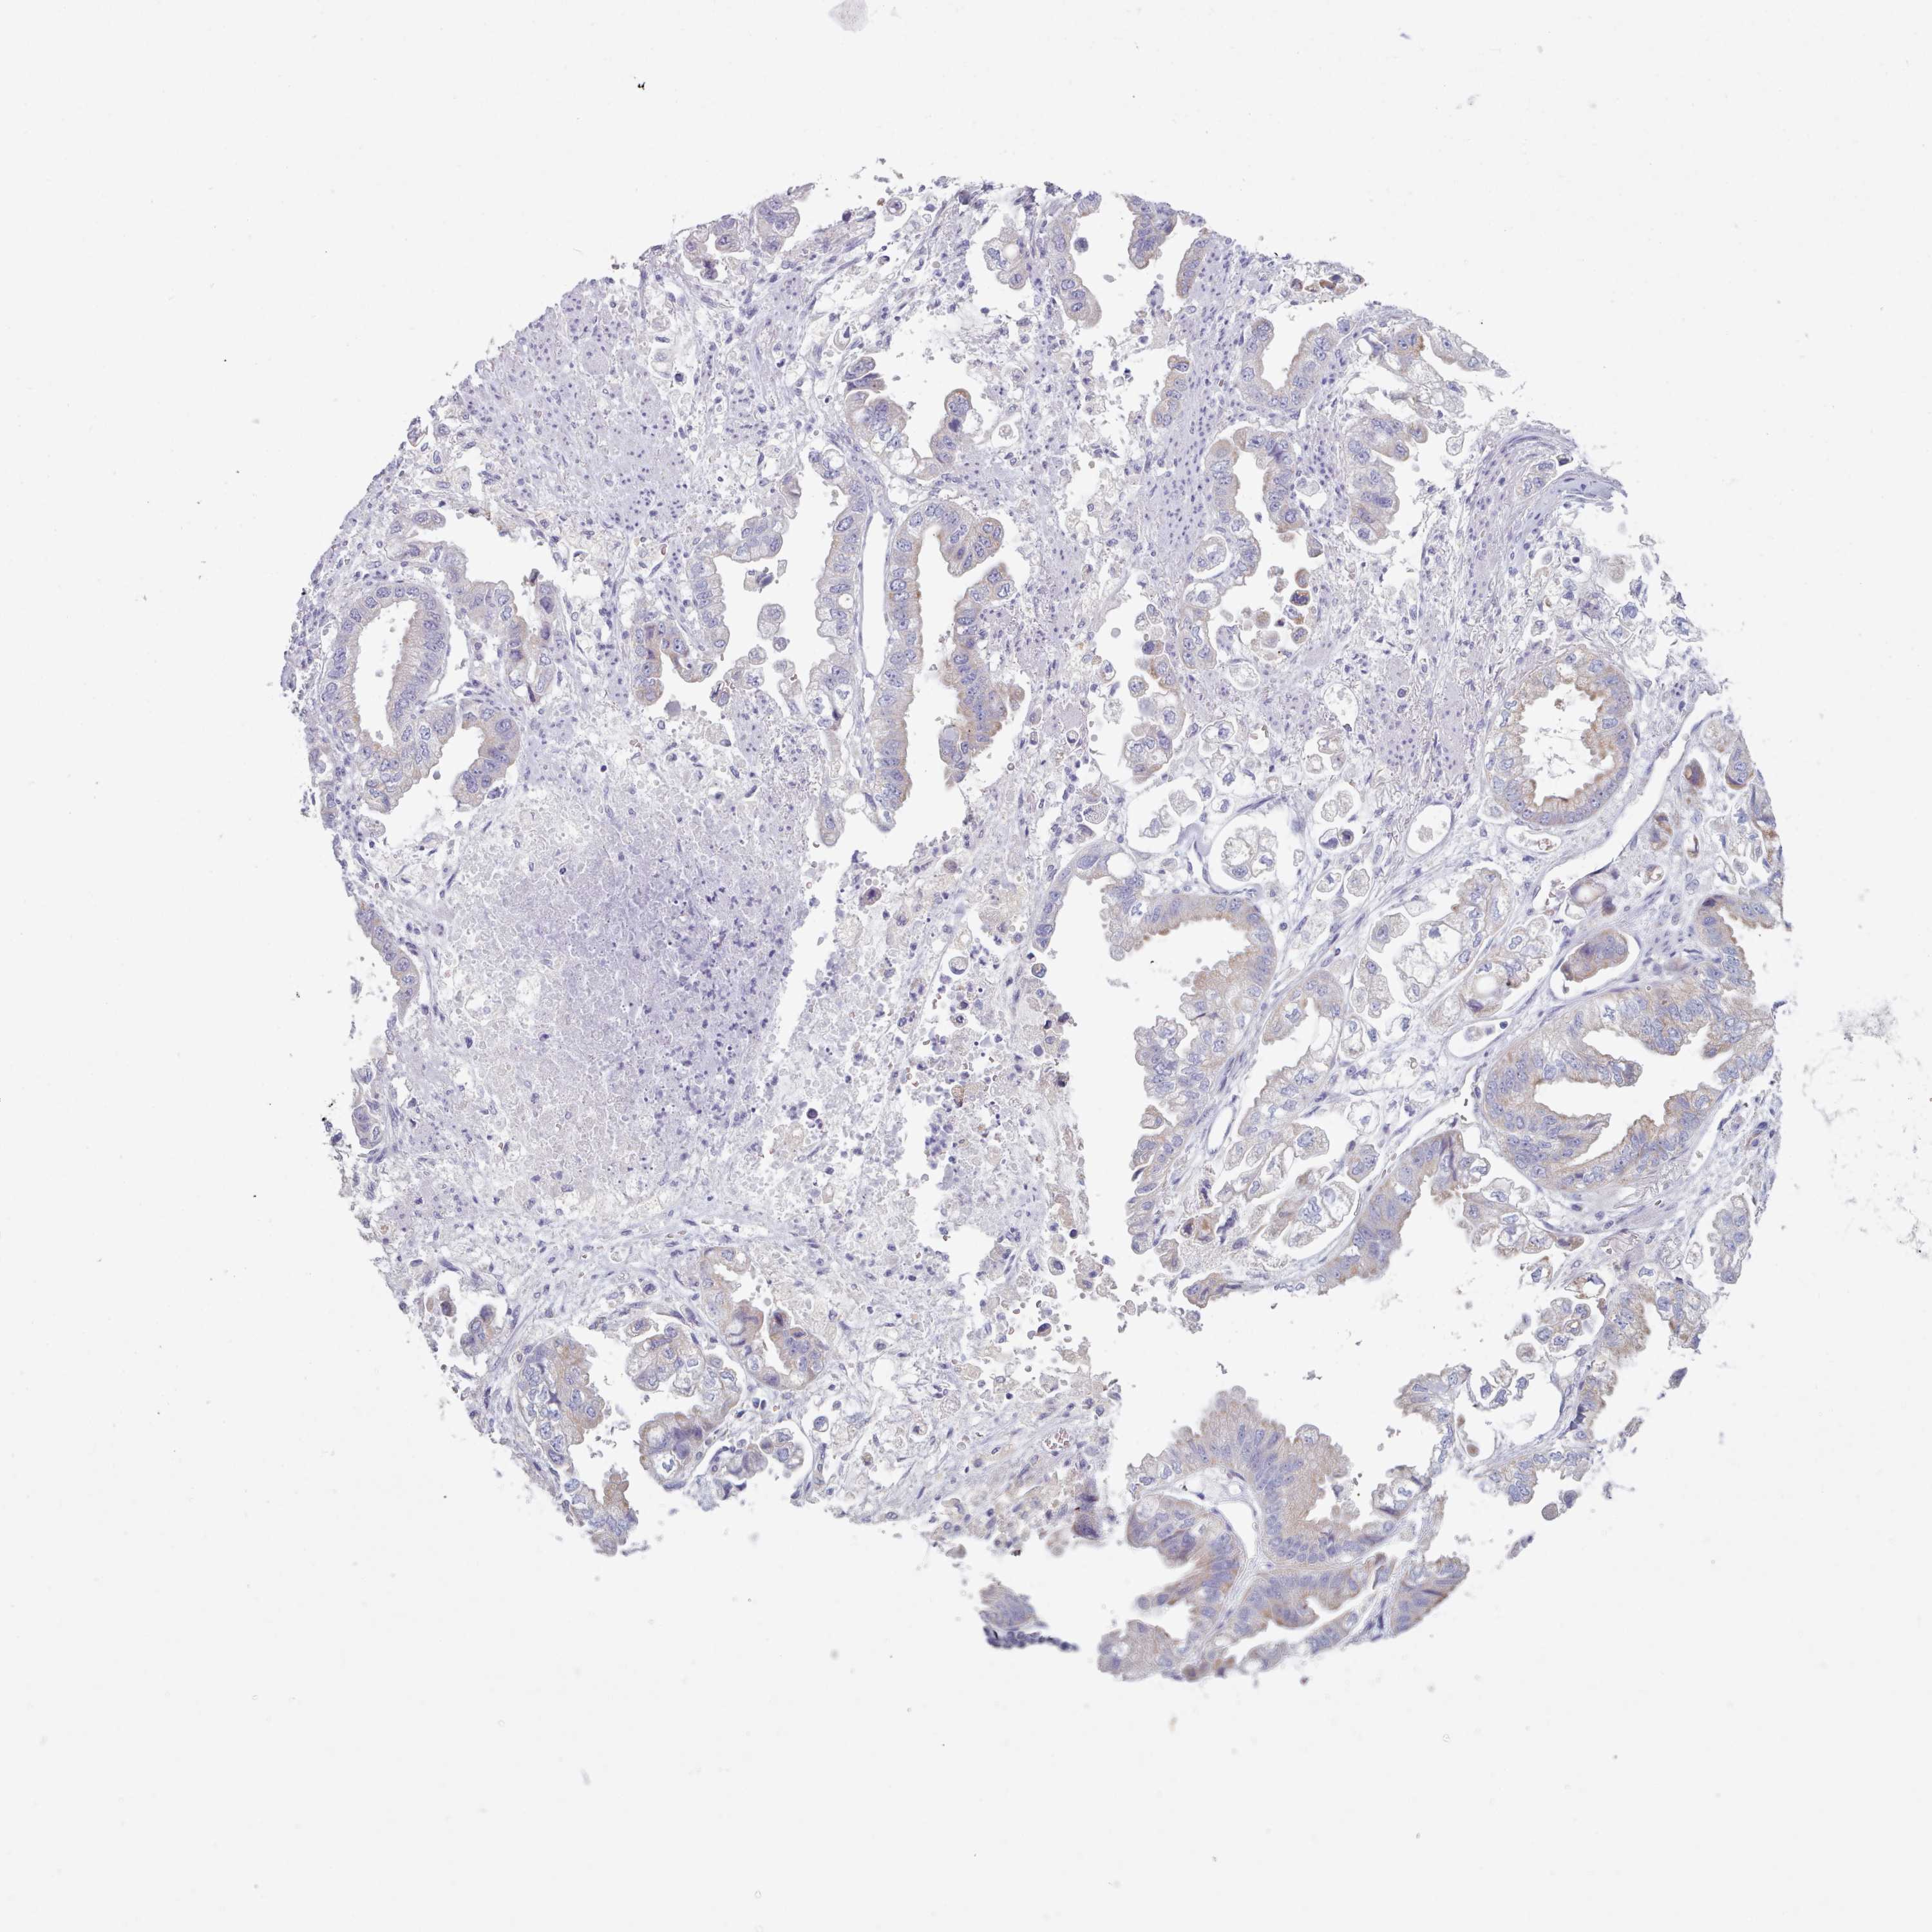

STOMACH CANCER - Protein expressioni

A mouse-over function shows sample information and annotation data. Click on an image to view it in a full screen mode. Samples can be filtered based on level of antibody staining by selecting one or several of the following categories: high, medium, low and not detected. The assay and annotation is described here.

Note that samples used for immunohistochemistry by the Human Protein Atlas do not correspond to samples in the TCGA dataset.

Antibody stainingi

Antibody staining in the annotated cell types in the current human tissue is reported as not detected, low, medium, or high, based on conventional immunohistochemistry profiling in selected tissues. This score is based on the combination of the staining intensity and fraction of stained cells.

Each image is clickable and will lead to virtual microscopy that enables deeper exploration of all samples and also displays staining intensity scores, fraction scores and subcellular localization as well as patient and tissue information for each sample.

Antibody HPA049552

Antibody HPA072442

Staining

High

Medium

Low

Not detected

Intensity

Strong

Moderate

Weak

Negative

Quantity

>75%

75%-25%

<25%

None

Location

Nuclear

Cytoplasmic/membranous

Cytoplasmic/membranous,nuclear

Adenocarcinoma, NOS

Adenocarcinoma, High grade